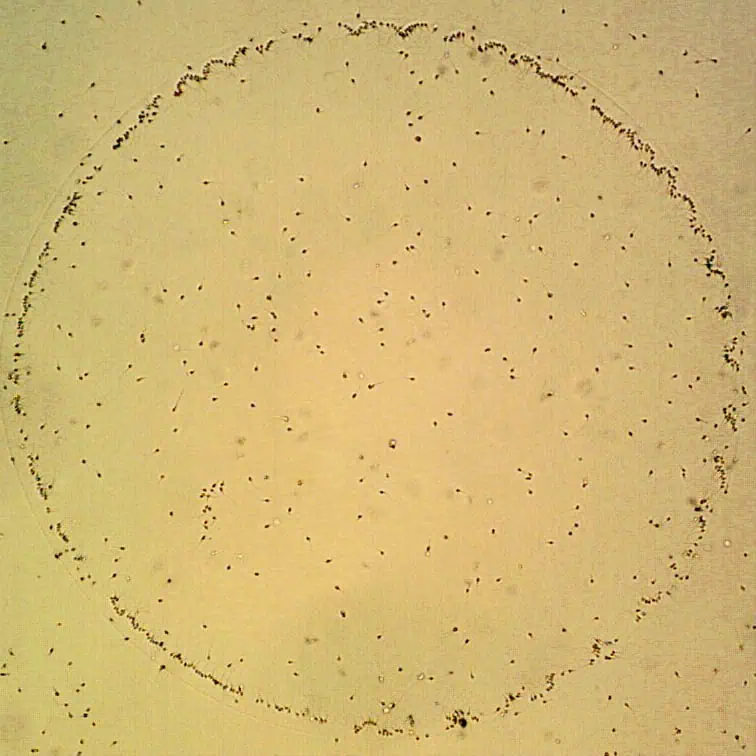

Při této metodě jsou spermie inkubovány v Petriho misce, jejíž dno je pokryté hyaluronanem. Pro ICSI jsou následně vybírány pouze spermie navázané na hyaluronan. Hyaluronan je mukopolysacharid, který se přirozeně vyskytuje jako součást mezibuněčné hmoty obklopující spolu s kumulárními buňkami vajíčko. Aby mohla spermie při přirozeném oplození úspěšně proniknout do vajíčka a oplodnit ho, musí být schopna vázat se k hyaluronanu. Takové interakce je schopna pouze zralá spermie. Vědeckými studiemi bylo potvrzeno, že spermie, které jsou schopny vazby k hyaluronanu, mají lepší morfologii, statisticky nižší podíl chromozomálních anomálií a lepší integritu DNA.